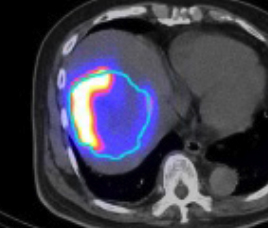

- Pre-treatment Tc-99m MAA SPECT/CT

- Predict distribution ratio of tumor-to-nontumor Y-90 microsphere on post-treatment Y-90 SPECT/CT

- Identify shunting to lungs or viscera

- Y-90 Liver Selective Internal Radiation Therapy (SIRT)

- Tc-99m MAA (Left) to simulate Yttrium-90 particle distribution

- Evaluate treatment feasibility

- Calculate Prescription Dose from dual tracer PET/CT

- Use PET/CT to scan Yttrium-90 particle distribution (Right)

Pre-treatment Tc-99m MAA SPECT/CT Post-treatment Y-90 PET/CT